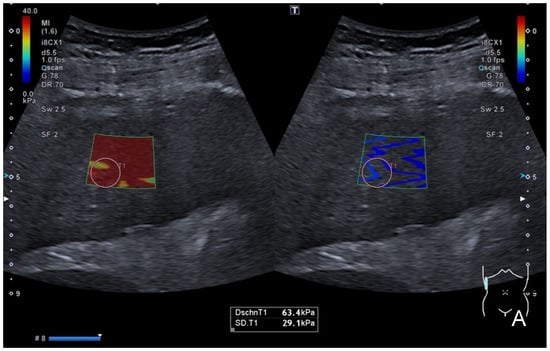

After entering the SWE mode, a sample box was placed at an adequate depth, and the SWE’s images and loops were acquired using the standardized breath-hold technique. The homogeneity of the color-coding inside the sample window, as well as a separately provided homogenous wave-propagation image, served as indicators of the quality of the SWE measurements. If no homogenous image could be obtained, the position was altered and the procedure was repeated. In SWE, repetitive acoustic radiation force impulses (ARFIs) are applied in cycles, inducing shear waves in the targeted tissue. Shear waves can be visualized in color-coded maps and their speed can be measured, which correlates with the tissue’s stiffness [1]. To obtain reproducible and quantifiable measurements, a total of five regions of interest (ROIs) sized 10 mm × 10 mm were placed in each case inside the color-coded SWE map in equivalent positions, and the shear-wave speed (SWS) in m/s, and the stiffness in kPa were measured. Mean values (±sd) for SWS and stiffness were calculated from 5 to 6 single measurements. A cut-off value for the detection of liver steatosis using SWE was calculated and applied. The SWE measurements were correlated to the PDFF’s fat-signal-fraction measurements. An example of the application of SWE is provided in Figure 1.

Figure 1.

Intercostal view in an SWE application (left in (A,B)) with corresponding shear-wave dispersion (right in (A,B)) in a patient with severe liver fibrosis/cirrhosis. (A) displays a color-coded elastogram representing the elevated stiffness (red colorization of the sample window), which was confirmed in quantification measurements after placing a sample ROI inside the SWE box which presented stiffness values of 63.4 kPa and an SWD of 14.2 m/s/kHz (C). (B) shows the corresponding SWS mapping of the same patient with an inhomogenously colored elastogram, representing elevated shear-wave speed values in this case of advanced cirrhosis, which was confirmed in quantitative analysis (SWS = 3.69 m/s). The validity of acquired measurements was confirmed using the dispersion slope form as a quality indicator. (C) provides corresponding quantitative “liver analysis” results: mean and median values (±sd) of the SWE, the SWD and the ATI were calculated (white box), and the classification of individual findings was performed according to the color-coded scale (white arrow). This patient’s measurements were classified as “severe” considering the SWE, “significant” considering the SWD and “normal” considering the ATI analysis, suggesting the presence of severe fibrosis or cirrhosis but only little inflammation or steatosis.